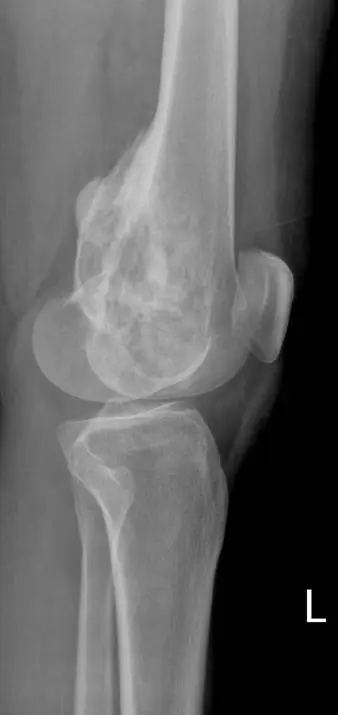

本題提供左膝關節正位(AP)及側位(lateral)X 光片兩張(標記「L」):

側位片(lateral view):

- 確認股骨遠端後方的大範圍皮質破壞與軟組織延伸

- 腫瘤侵犯範圍橫跨股骨遠端大部分骨幹

- 硬化性骨基質形成與